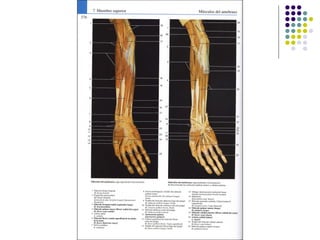

La extremidad superior humana incluye el hombro, el brazo, el codo, la muñeca y la mano. Está diseñada para una variedad de funciones motoras finas como agarrar objetos y realizar tareas manuales complejas. La coordinación precisa de los músculos y los huesos de la extremidad superior es clave para su versatilidad funcional.